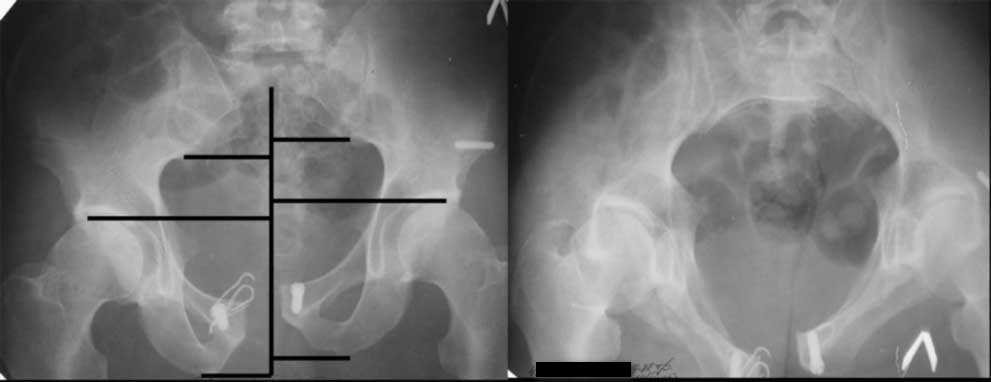

Дорогой Андрей. Мы имеем дело с комбинированной (ротационно и вертикально) нестабильностью таза со смещением правого гнемипелвиса. При таких переломах, фиксация только переднего полукольца вне зависимости от метода фиксации, как уже было сказано Djoldas Kuldjanov, M.D., не может создать адекватной фиксации. И перелом пластины был вполне ожидаемым после активизации пациента. Смещение сохраняется, и по-видимому не 2 см., а все 4, если не более. Разница всего (+2 см) по конечностям как вы указываете, скорее скомпенсировано позвоночником и протезом. Дополнительные снимки или КТ исследование помогли бы уточнить степень смещения с точностью до мм., выявить перелом поперечного отростка пятого поясничного позвонка, или помимо разрыва правого крестцово-подвздошного сочленения выявить перелом боковой массы крестца справа и т.д. При возможности, конечно, все это желательно сделать. Но мало что изменится с практической точки зрения, т.к. задача - это низведение репозиция и надежная фиксация правого гемипелвиса. Учитывая плачевный опыт стержневого аппарата, давность травмы совершенно очевидно, что поставленная задача достижима при открытой репозиции и одномоментной фиксации переднего полукольца с артродезированием правого крестцово-подвздошного сустава. Операция выполняется в положении больного на здоровом боку или полубоку из расширенного трансоссального подвздошно-пахового доступа с переходом на лонное сочленение доступом по Pfannenstiel. Указанный доступ обеспечивает подход к крестцово-подвздошному сочленению как спереди так и сзади. После артродезирования выполняется синтез лонного сочленения. Клинический пример

Пациентка С.26 лет. Травма за 6 месяцев до поступления

Укорочение правой нижней конечности до 10см

23.09.2003. Одновременный остеосинтез переднего и заднего тазовых полуколец

Результат через 10 дней

и 8месяцев после операции